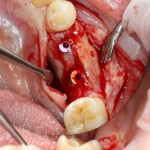

Исходная клиническая ситуация: из-за длительного отсутствия зубов возникла существенная атрофия альвеолярного гребня по толщине:

A09A5442 (2)  A09A5443 (2)

Операция начинается с разреза. Напомню, что разрез делается в пределах прикрепленной десны, это важно для последующего соблюдения Фактора успеха III:

A09A5444 (2)

Скелетирование альвеолярного гребня. В том числе, участка для забора аутокостного трансплантата:

A09A5445 (2) A09A5446 (2)

Следующим этапом происходит формирование и забор аутокостного фрагмента для пересадки:

A09A5447 (2) A09A5448 (2)

Далее, примеряем и адаптируем костный блок:

A09A5449 (2) A09A5450 (2)

Готовим его к фиксации:

A09A5451 (2)

Фиксация костного блока:

A09A5452 (2) A09A5453 (2)

Теперь можно готовить лунки под импланты:

A09A5459 (2)

В данном случае я планирую установить импланты Nobel Replace Conical Connection:

A09A5461 (2) A09A5462 (2)

Операция почти закончена. Обратите внимание, на два момента:

1. Блок явно больше, чем нужно. Это связано с тем, что в процессе интеграции происходит атрофия графтов (причем, абсолютно любых), и мы должны закладывать этот уровень атрофии при планировании объемов костной пластики. В среднем, плюс 30% к тому, что нам нужно.

2. Между блоком и принимающим ложем есть пустое пространство. Поэтому область операции необходимо изолировать барьерной мембраной от быстро растущих мягких тканей. Я использую Geistlich BioGide 25×25 mm:

A09A5466 (2) A09A5467 (2)